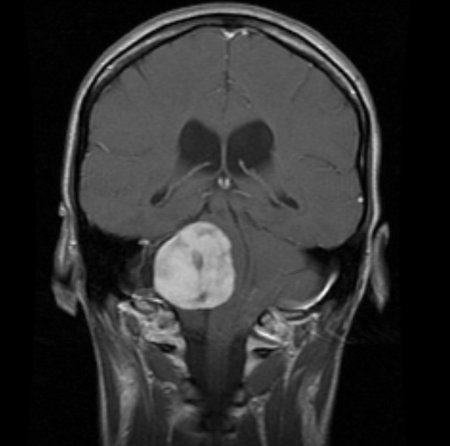

Craniofaringioma: ressonância nuclear magnética (RNM) coronal pós-contraste

Do arquivo pessoal de Marc C. Chamberlain; usado com permissão